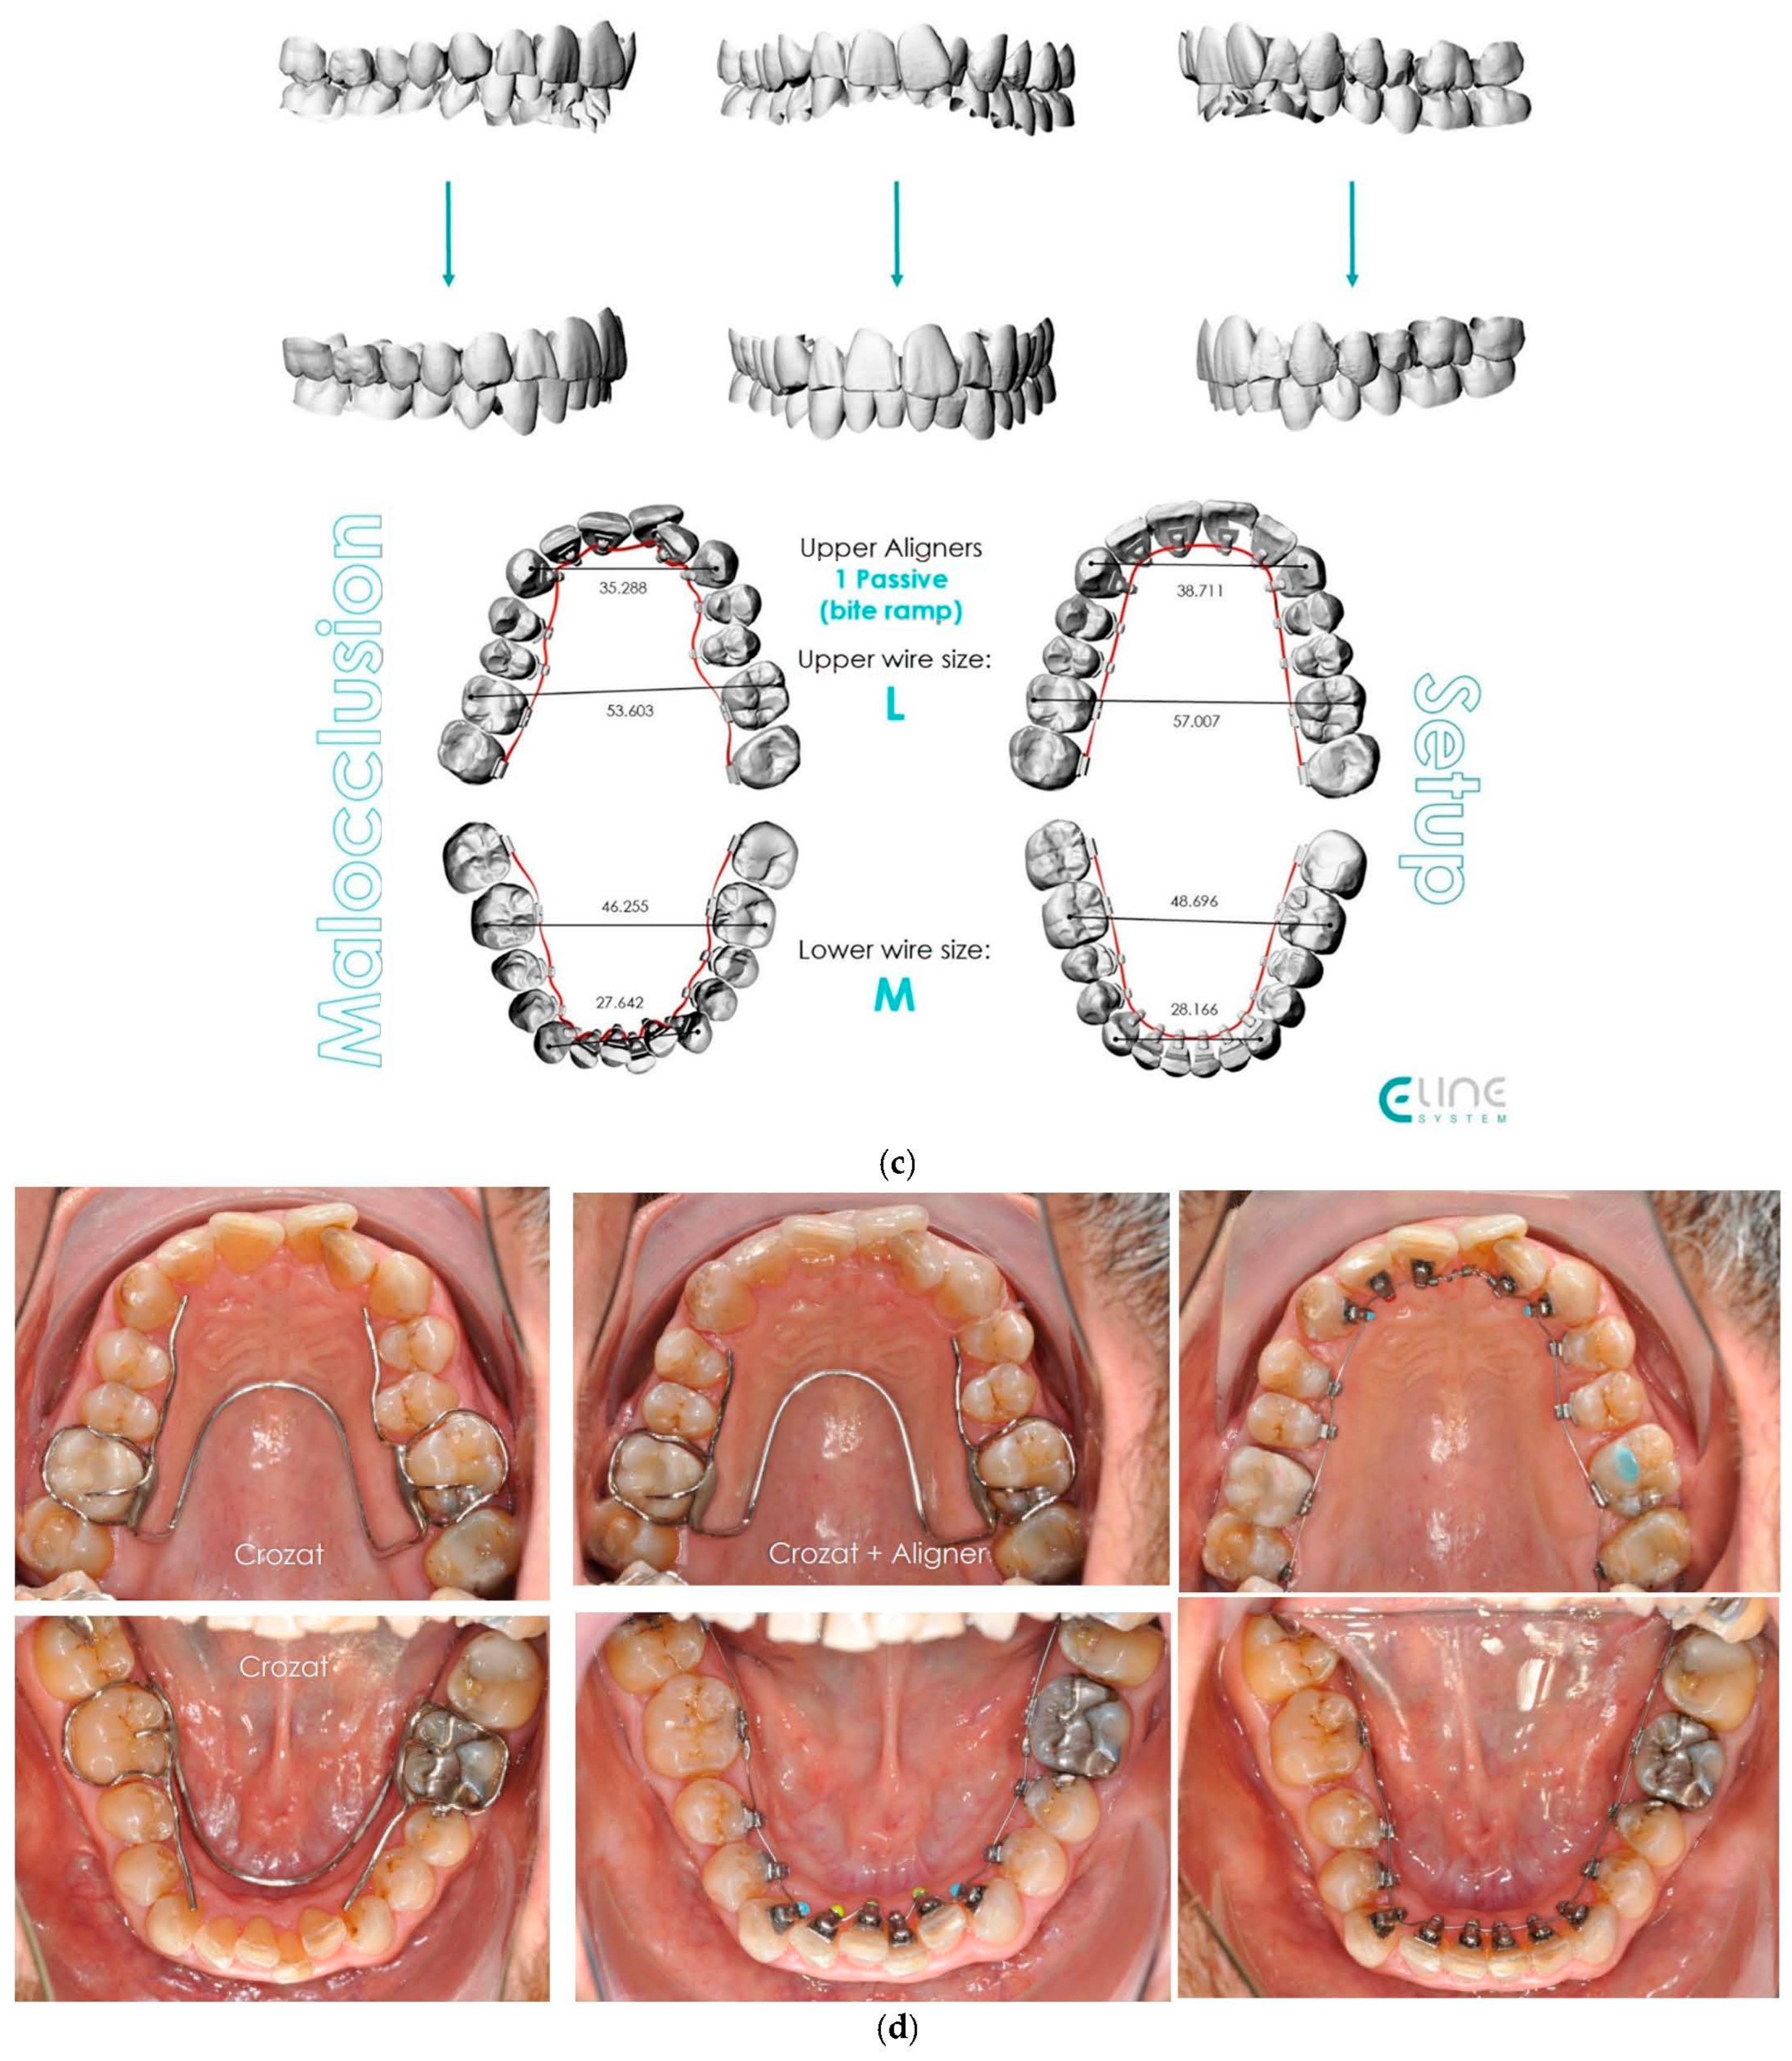

Figure 5.

(a,b) The initial images of the profile and frontal smile view and intraoral images and radiographs, including panoramic radiographs and a lateral cephalogram. (c) The digital setup performed for the treatment. (d,e) The treatment in progress with a Crozat appliance along with the aligners and lingual appliances. (f–h) Post-treatment images and a comparison with the initial images. (i) A superimposition of the pre- and post-treatment cephalograms.

The treatment objectives were to resolve the dental Class II malocclusion and achieve a Class I canine and molar relationship; eliminate the crowding, creating space for alignment, without extraction; and correct the deep bite and thereby improve the facial profile. The treatment plan chosen was a hybrid approach and IPR. The upper arch was treated initially by a Crozat appliance to achieve transversal expansion and by aligners with bite ramps to disocclude posteriorly and enhance the expansive effect of the Crozat. In the second phase, the upper arch was also bonded with Alias lingual brackets that were treated with the following archwire sequence: 0.014- and 0.016-inch CuNiti for levelling and alignment; 0.016 × 0.016-inch and 0.018 × 0.018-inch CuNiTi for rotational, tip and torque control; 0.017 × 0.017-inch SS for archform stabilisation; and 0.0175 × 0.0175-inch TMA for space closure and intrusion by loop mechanics and detailing.

In the lower arch, a Crozat appliance was used initially, followed by an Alias PSL lingual fixed appliance with the following sequence of archwires: 0.013- or 0.014- and 0.016-inch CuNiti for levelling and alignment; 0.016 × 0.016-inch and 0.018 × 0.018-inch CuNiTi for rotational, tip and torque control; 0.017 × 0.017-inch SS (stainless steel) for arch form stabilization and space closure; and 0.0175 × 0.0175-inch TMA for detailing.

Although the correction of transverse discrepancies with good torque control is challenging with both lingual and aligner techniques [24,34,38], Case 3 (Figure 5) had a similarly successful outcome. In that case, the treatment required significant transverse expansion, along with the elimination of the deep bite and resolution of the crowding in both arches. A Crozat appliance and a partial aligner with a bite ramp/plane was used for the initial four months. Temporarily opening the posterior bite enhanced the expansive effect of the Crozat and facilitated levelling of the lower curve of Spee via the direct use of lingual appliances on the mandibular arch. The intermolar width in the upper arch was increased from 53.6 mm to 57 mm and in the lower arch from 46 mm to 48.7 mm.

Once the expansion and deep bite correction had been accomplished, lingual appliances were bonded to align the upper arch, control the upper anterior inclination and torque (perfecting the crossbite), perform intrusion and control the lower incisor inclination.